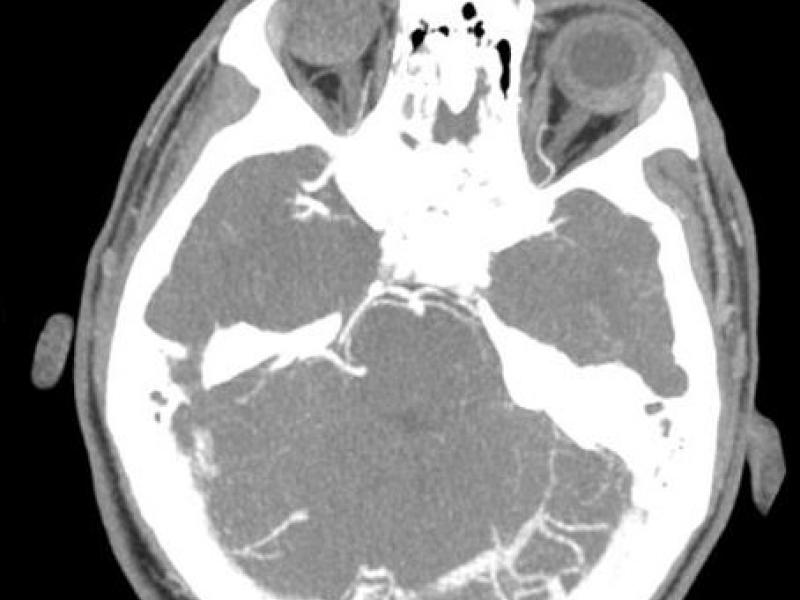

What's the Diagnosis? By Dr. Katie Selman

January 16 2019

A 15 yo M presents to the ED with headache x 3 days. He

EM Daily